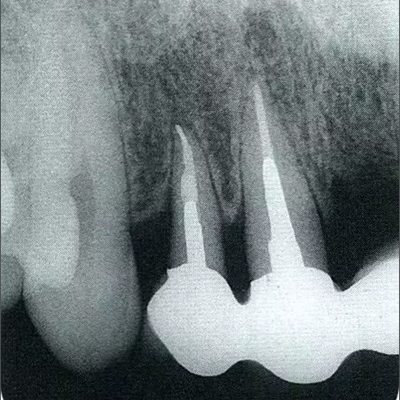

深牙周袋的治療

圖10-10  術(shù)后2年的x片。確認(rèn)骨水平獲得改善,牙周探診值在2mm以下